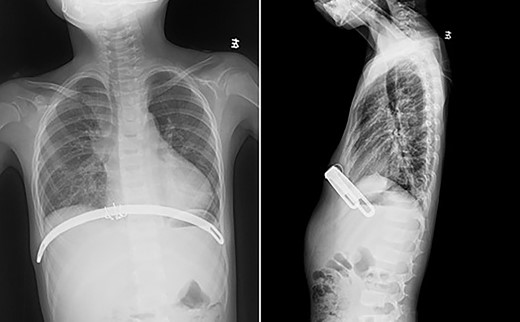

The patient was a 7-year-old boy. Two years ago, he underwent surgical treatment for pectus excavatum in a local hospital. At that time, Wang procedure was used and a steel bar was implanted. After the operation, the steel bar was displaced and the depression recurred (Figs 1 and 2), so the steel bar had to be taken out 1 year after the operation. After removal, his anterior chest wall still had obvious depression, and there was a tendency to aggravate. In order to completely correct the deformity, the patient was recently admitted to our hospital for surgery. Preoperative physical examination showed that the anterior chest wall was asymmetrically depressed, and the deepest depression was located in the right chest wall (Fig. 3). There was a scar in the middle of the anterior chest wall (Fig. 3). Preoperative imaging examination showed that the anterior chest wall was depressed, the heart was obviously compressed and moved to the left (Fig. 4). The operation was performed under general anesthesia. Supine position was adopted, with abduction of both upper limbs. Two incisions were made on both lateral chest wall respectively, which were located at the deepest plane of the depression. The muscles were dissected to expose the ribs in the incision. The depression was eliminated by Wung procedure, which was performed as follows [2]: A tunnel at the deepest plane of the depression was made. A special guider was inserted directly through the gap between the sternum and the heart, and then a steel bar introducing tube was connected with the guider. After the introducing tube was pulled into the body by the guider, a special steel bar was pulled by the introducing tube to the bottom of the depression. After the steel bar was rotated, the depression was supported, but the left chest wall began to be protrusive. In order to make the anterior chest wall more beautiful, Wenlin procedure was performed next [3, 4]. An incision at the median scar was made, and a tunnel was built from the median incision to the incision on both sides, which was located between the bone structures and the chest wall muscles. The second steel bar was inserted into the tunnel. After the protrusive part of the anterior chest wall was pressed with the middle part of the steel bar, both sides of the bar was fixed to the ribs on the lateral chest wall. Drainage tubes were placed in the thoracic cavity on both sides, the incision was closed, and the operation was completed (Fig. 5). No complications occurred during the operation. The total operation time was 50 min and the intraoperative bleeding volume was 5 ml. Postoperative X-ray examination showed that the positions of the steel bars were satisfactory and the shape of the chest wall was basically normal (Fig. 6). The patient was discharged 5 days after operation. Follow up for 1 month showed no change in thoracic shape and no discomfort.